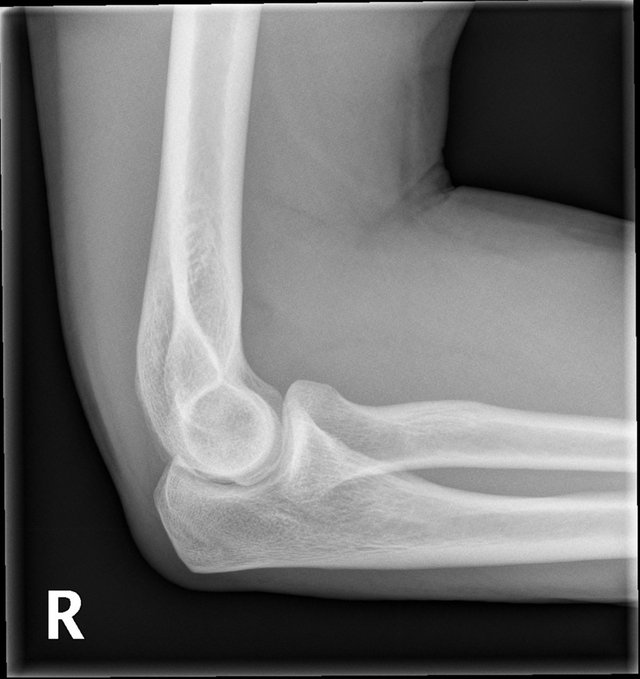

Let’s look at the X-Ray below…

So, let's go through some questions...

- What joint is this?

- Which side of the body?

- What angle are we looking from?

- How old is our patient?

- Is this image normal?

Well let's start at the top...

- This is an elbow

- This is the right elbow (this can be hard to tell on X-Ray, look for the tell-tale 'R')

- We're looking from a lateral view, that means from the side

- Here we really only need to break down between children, and not children. A child's bone will not fully 'ossify' (harden) till they finish puberty and till this age, the un-hardened bone will have see-through sections... so this is an adults bone.

- Yes it is normal, and let's look at why...

This is what we are looking at